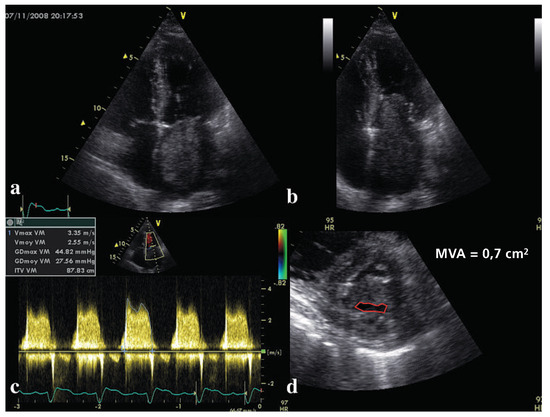

Description du cas